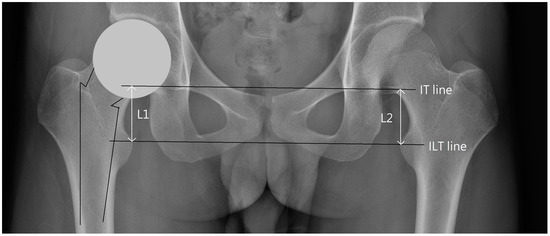

| The Outliers We Removed | Image Features |

|---|---|

| Outlier 1 of ∠RSC | Uneven protrusions on bilateral iliac crests. |

| Outlier 2 of ∠RSC | Normal |

| Outlier 1 of ∠RBI | Poor image quality, but borders of the pelvic landmarks are still visible. |

| Outlier 2 of ∠RBI | Right side femur fracture without femoral head dislocation. |

| Outlier 1 of ∠RIT | Asymmetrical teardrop shapes on both sides. |

| Outlier 2 of ∠RIT | Asymmetrical teardrop shapes on both sides. |

| Outlier 1 of ∠RUO | Normal |

| Outlier 2 of ∠RUO | The obturator foramen is slightly distorted on the image. |

| Outlier 1 of ∠RLO | Normal |

| Outlier 2 of ∠RLO | Normal |